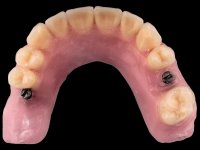

To fabricate overdentures supported and retained by milled bars screwed over the dental implants.

Then, the teeth were mounted in the screwed record bases and function and aesthetics were clinically evaluated. After these evaluations, the dental technician develops silicone walls that guide the fabrication of the milled bars. The precise passive fit of the bars was checked clinically and with radiographs. Then, a pick-up impression with an individualized tray was done to achieve a functional impression of the soft-tissues.